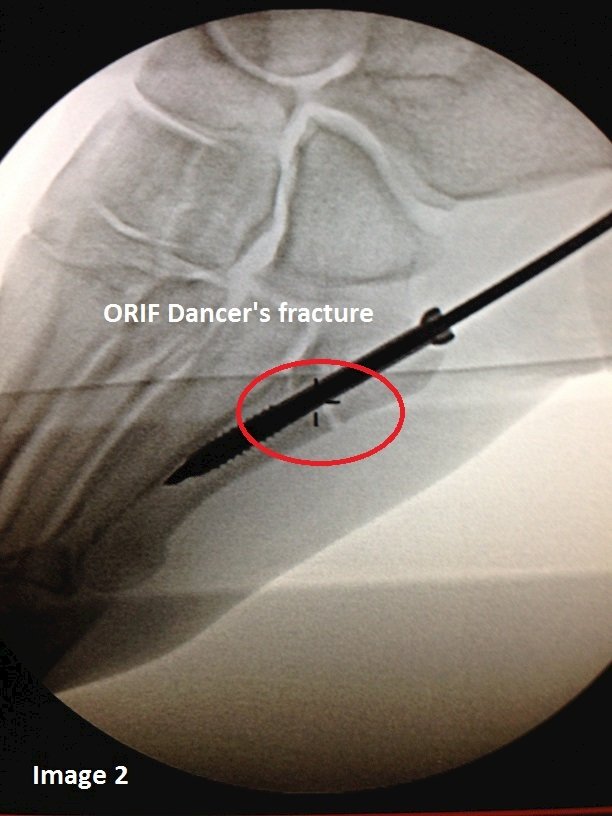

Case #1 is a 6’ 7” police officer. At 42 years old, he’s active, non-smoker and fit. The location of the fracture (as seen in image 1) is at the demarcation of the metaphyseal bone and diaphyseal bone. As you can see in the image, I took him to surgery for a percutaneous closed reduction using a 6.5 mm cannulated bone screw. Even with internal fixation, the patient will be 8 weeks non-weight bearing and follow with 4 weeks in a walking cast.